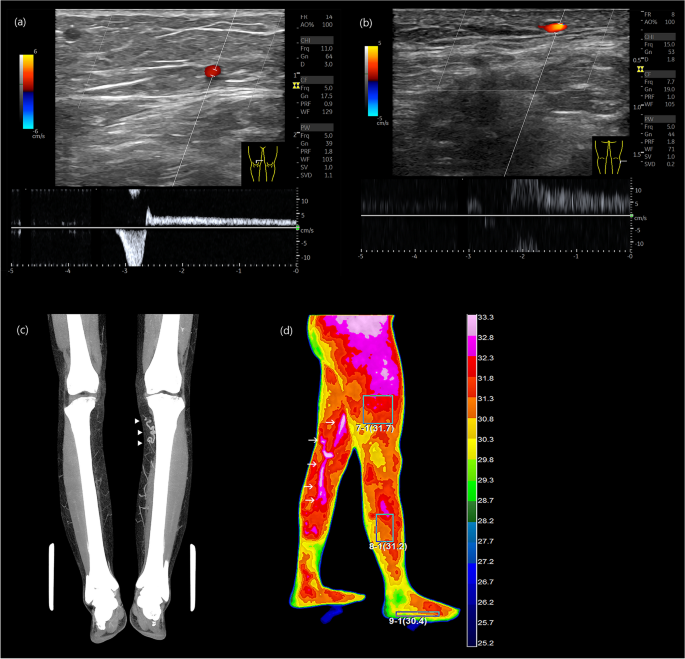

The standard tool for CVD confirmation is visualizing venous reflux wave on the duplex ultrasound examination (Fig. 4a)10, 11. Essential procedures include visualization of the venous flow, provocative maneuvers to assess reflux, and augmentation of flow. Recent advance of ultrasound resolution and fine probes have made it possible to detect small symptomatic reflux flow as small as 1–2 mm in size (Fig. 4b).

Diagnosis of CVD. (a) Axial ultrasound image showing GSV reflux at right lower thigh, (b) Axial ultrasound image displaying direct tributary reflux at right lateral calf, (c) Venous phase of lower extremity CT revealing a tortuous GSV at left upper calf indicating varicose change (arrowhead), (d) DITI showing GSV reflux at left medial thigh and calf (arrow).

The contrast-enhanced lower extremity computed tomography (CT) scan is useful for visualizing entire vascular pathway and tortuous varicose change of leg veins (Fig. 4c). It has superior capability than the ultrasound for visualizing complex saphenofemoral junction and superficial venous pathway variation. It is useful to find other vascular conditions such as arterial stenosis, occlusion, and deep vein pathology. Digital Infrared Thermographic imaging (DITI) is also a useful auxiliary diagnostic tool. Elevated temperature signal changes along known venous pathways or symptomatic locations are strong clues for the presence of venous reflux (Fig. 4d).